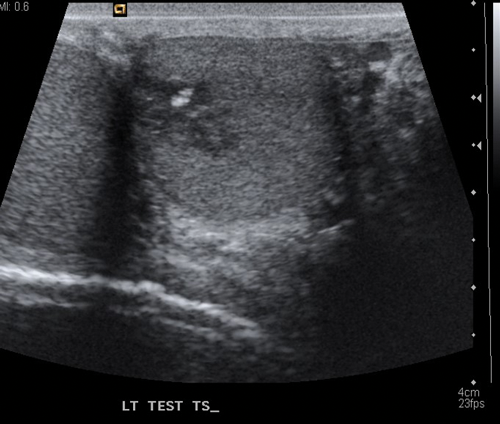

Figure 1. US of seminoma seen as a multi-septated area of low attenuation with a lobulated outline.

Seminomas can have a uniform appearance and are generally of low echogenicity but larger tumours may be heterogenous and lobulated (Figure 1). Typically, teratomas are described with areas of calcification and are heterogenous, also containing fluid. They can have areas of central necrosis and haemorrhage (Figure 2). Both tumours are classically hypervascular, but depending on areas of fluid or necrosis may be hypovascular. Lymphoma tends to be infiltrative involving the whole testis and causing diffuse testicular enlargement rather than a more focal tumour.